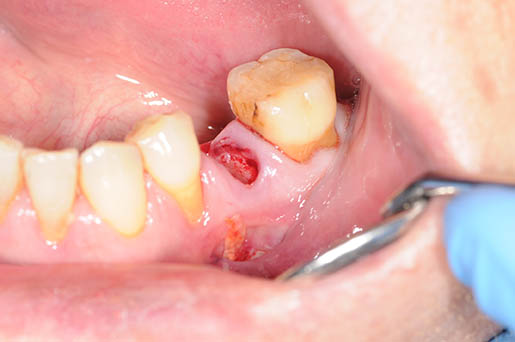

Chirurgia

L’approccio chirurgico prevede l’asportazione dell’osso necrotico ed è generalmente consigliato per gli stadi più avanzati e o terminali della MRONJ.

L’intervento chirurgico rappresenta il rischio di recidiva con estensione delle aree di esposizione ossea e aggravamento dei sintomi. Diverse alternative e terapie aggiuntive (laser a basso livello, ossigeno iperbarico, ozono terapia) e diversi agenti biologici (contribuzione piastrinica autologa, concentrati, fattori di crescita e differenziazione ricombinanti, ormone paratiroideo) sono stati proposti in letteratura con risultati positivi.

Programmare un’ intervento chirurgico dovrebbe quindi rappresentare l’ estrema ratio per la risoluzione di questa problematica.

Gli interventi chirurgici dovrebbero quindi essere indirizzati quindi a trattare in sala operatorie i pazienti che non solo necessitano di rimuovere le aeree osteonecrotiche ma al contempo anche la necessità di ad esempio utilizzare placche di fissaggio ed osteosintesi per evitare conseguenti problematiche come fratture e/o resezioni en-block e innesti ossei maggiori ( fibula, cresta iliaca, teca cranica,…)

Intervento chirurgico in narcosi